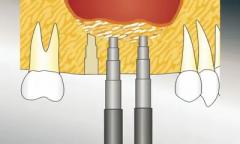

Sinuslift

Beim frühzeitigen Verlust von Seitenzähnen im Oberkiefer dehnt sich die Kieferhöhle aus. Der Knochen reicht nicht aus, um ein Implantat tragen zu können. Die Kieferhöhle wird durch ein seitliches Fenster eröffnet. Die Kieferknochenschleimhaut wird mit Hilfe spezieller Instrumente in die Kieferhöhle angehoben.

Dadurch entsteht ein Hohlraum, der mit Knochenersatzmaterialien aufgefüllt wird. So wird der knöcherne Boden der Kieferhöhle verstärkt, um dem Implantat einen besseren Halt zu geben. Nun kann der Zahnersatz darauf befestigt werden.

Bei geringerem Bedarf an zusätzlicher Knochenhöhe kann das Anheben auch über die Implantatbohrung erfolgen. Dieser Eingriff ist dann kleiner und nur noch gering unterschiedlich zur normalen Implantation.